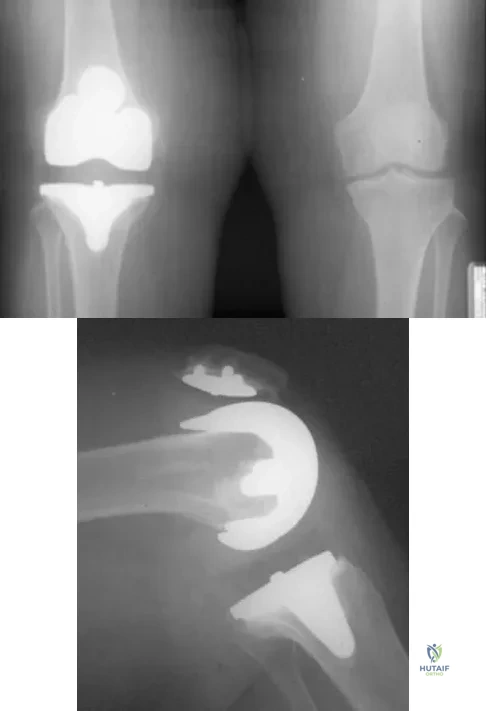

A 63-year-old woman reports giving way of the knee and pain after undergoing primary total knee arthroplasty (TKA) 1 year ago. Examination reveals that the knee is stable in full extension but has gross anteroposterior instability at 90 degrees of flexion. The patient can fully extend her knee with normal quadriceps strength. Studies for infection are negative. AP and lateral radiographs are shown in Figures 12a and 12b, respectively. What is the appropriate management?

A 58-year-old woman is seen in the emergency department after falling at home. History reveals that she underwent right total knee arthroplasty 2 years ago. Radiographs are shown in Figures 56a and 56b. What is the most appropriate treatment?